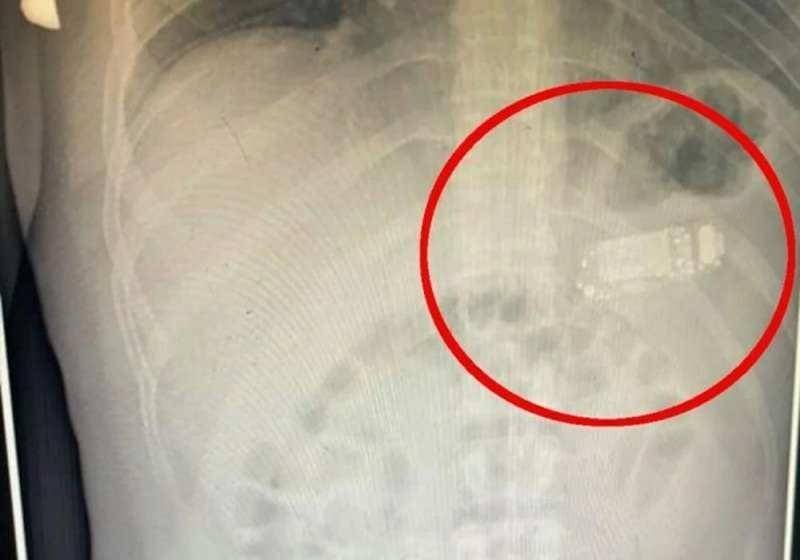

Başarılı operasyonu gerçekleştiren sağlık ekibinin başındaki doktor Skender Teljaku, adamın midesinden çıkarılan telefonun fotoğrafları ile röntgen ve endoskop görüntülerini Facebook'ta yayınladı.

Teljaku yaptığı açıklamada, tıbbi ekibin telefonu mideyi kesmeden, endoskop olarak bilinen özel cihazlar kullanarak üç ayrı parçaya ayırmayı başardığını söyledi. Teljaku, ayrıca yaklaşık iki saat süren işlem sırasında "herhangi bir komplikasyon" yaşanmadığını sözlerine ekledi.

Bununla birlikte 33 yaşındaki adamın telefonu yuttuktan sonra yaşadığı acı nedeniyle Kosova'nın başkentindeki hastaneye gitmeye karar verdiği aktarıldı. Teljaku, özellikle bataryanın en tehlikeli parçası olduğunu, patlayarak hayatı potansiyel olarak tehlikede olan adamın bağırsaklarına kimyasal salabileceğini söyledi.